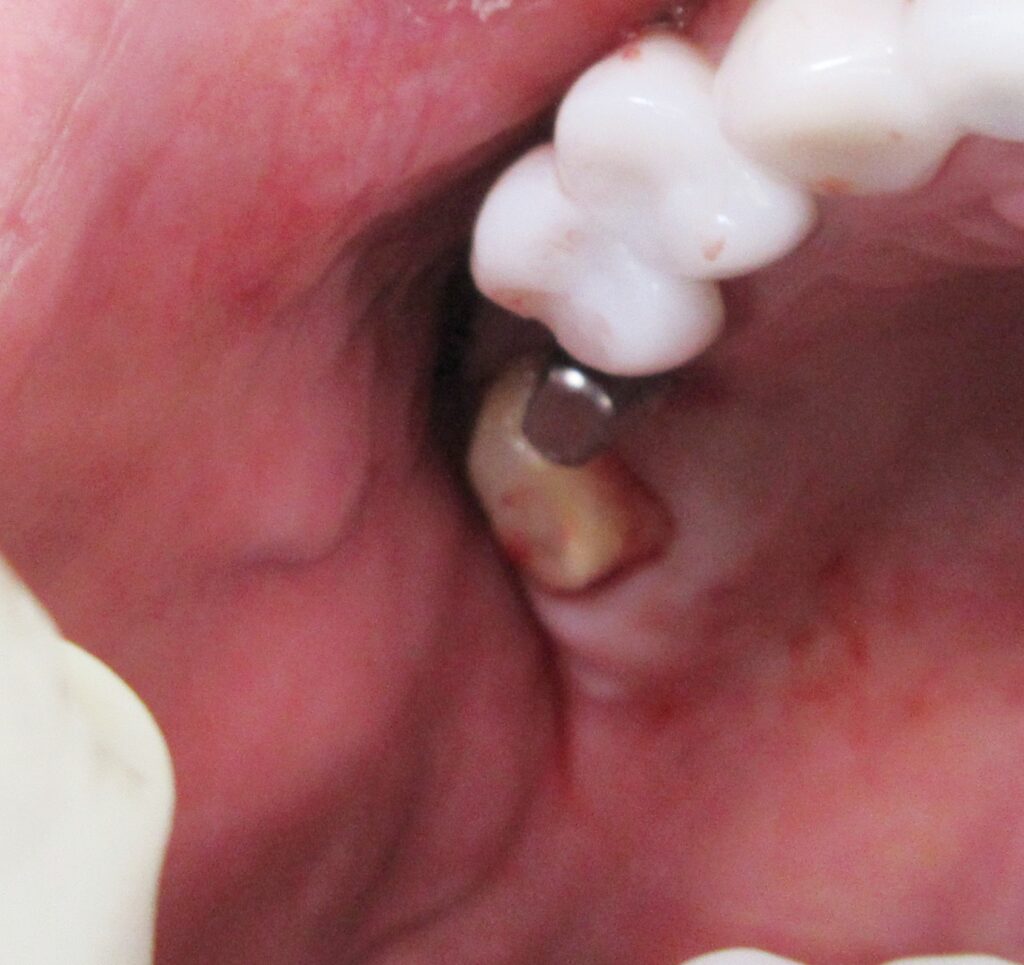

右上6番目の歯茎から骨の部分までを穴開けパンチの要領で穴を開けていきます。

くりぬいた部分の歯肉を取り除き、次は骨に穴を開けていきます。